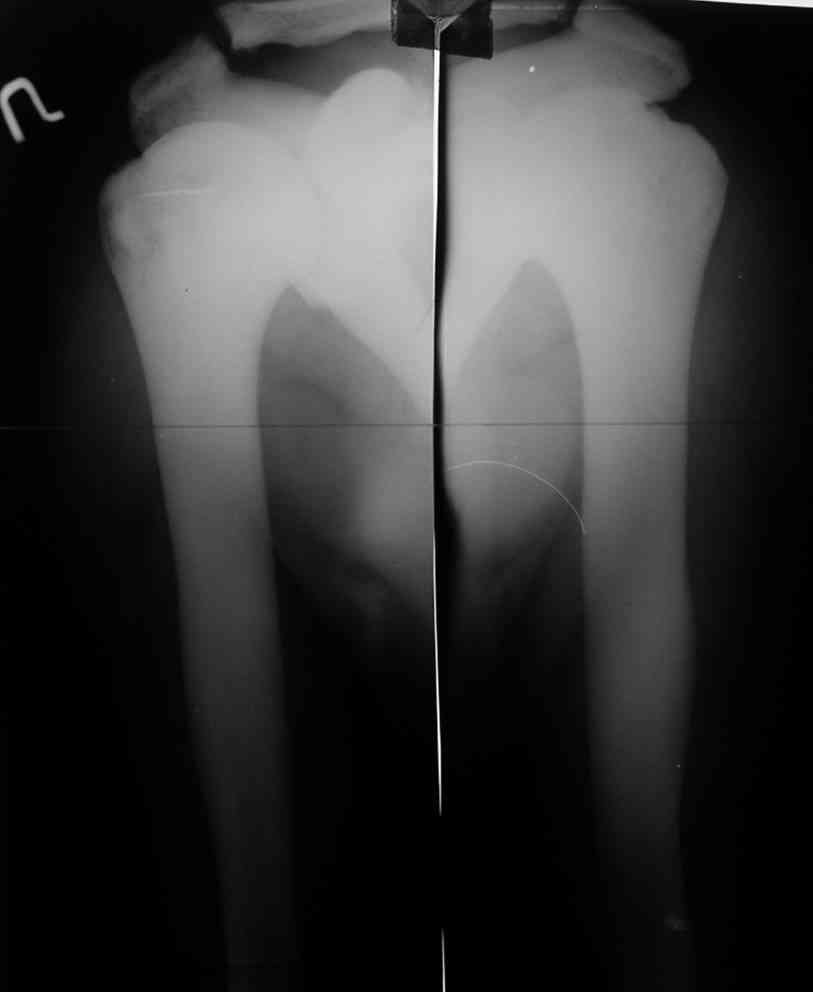

Уважаемый Константин Иванович! Полностью согласен с проф. Михайловым,

данный случай не похож на мраморную болезнь, при которой имеется

резкое, строго симметричное и генерализованное уплотнение костной

ткани (остеопетроз), и кость оказывается построенной преимущественно

из гомогенного компактного костного вещества. Для примера привожу

случай из архива нашего института (бедренные, плечевые кости и таз,

рис 1,2,3)